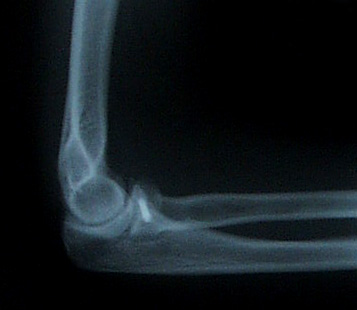

Straight Elbow I was awake during my elbow surgery, which was weird since I could hear Dr. Howson and her assistant debating about what size of screw to use, worrying about the pins slipping, and tapping at things with what sounded like a little hammer. (The pins were plastic and will disintegrate, but the screw will be with me forever.)

Bent Elbow